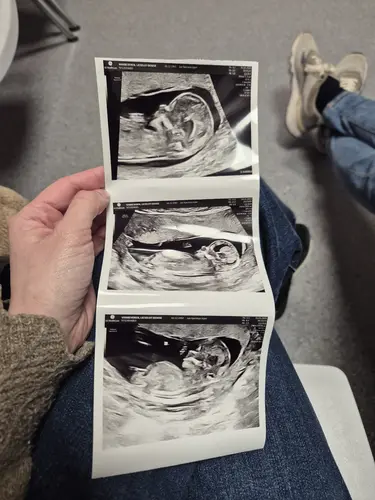

Zet je niet te veel vast op wat de nub theorie zegt. Zowel Ramzi theorie als nub theorie als scull theorie geprobeerd. Al mijn echo’s in chat gpt gezet. Hij was er zeker van dat het een jongen was. Ik zelf was dat ook al heel mijn zwangerschap. Is het een meisje volgens de nipt. Leuke theorieën maar zet er je niet op vast want het klopt niet. Je hebt 50% kans dat het klopt 😅

vorige week

Wij gingen voor de 12 weken (op 13weken) echo maar ik bleek eigenlijk al 14 weken te zijn. De echografist vroeg of we het geslacht al wilden weten en we schrokken dat dit al kon. Zij zei dat aan de hand van de nub theorie ze het kon zeggen met 80% zekerheid. Een jongetje dacht ze, eind volgende week hebben we de uitslag van de nipt en hopen eerst en vooral dat alles oke zal zijn en dan zullen we dus ook met zekerheid het geslacht weten. Ben benieuwd of het juist zal zijn! Ik was er wel van geschrokken dat de echografist zei dat die nub theorie dus wel “redelijk” betrouwbaar is! Ik probeer er allemaal niet teveel mee bezig te zijn, maar ik dacht dat dit een fabeltje was zoals de Ramzi theorie of de Chinese kalender.